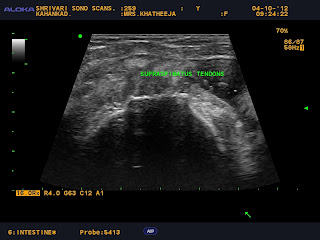

HR MSK US-Shoulder joint.--Rotator cuff injuries and degenerative changes

SUB DELTOID BURSITIS AND BICEPS TENOSYNOVITIS

BILATERAL SUPRASPINATUS  SYNOVIAL HYPERTROPHY